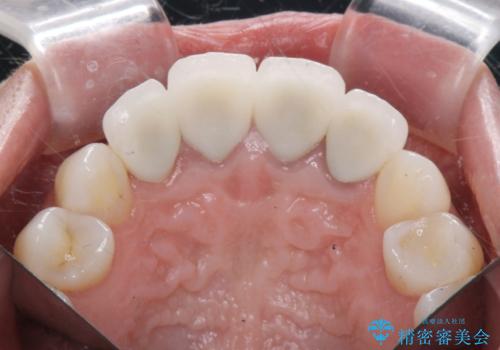

抜歯時に可及的に歯肉のボリュームを保つよう骨充填材とコラーゲン製剤による填塞を行い審美的かつ機能的なブリッジとなるよう治療を進めます。

- 66万円(ジルコニアクラウン×5・仮歯×5)費用は治療当時の料金となります

一件綺麗に見えるセラミックも適合や精度が悪いと、内部で虫歯が進行し亀裂や破折、悪臭の原因となることがあります。